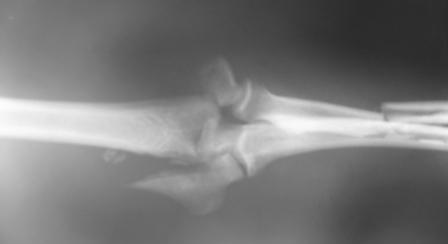

Все вроде бы удачно... Однако как говорят у нас ... вылечили в одной проекции, а как в другой? особенно сустав?. С Новым годом А Рыков Хабаровск.

Досылаю остальные снимки, вчера не смог их прикрепить из-за технических причин.

IMG_2649W.jpg

С Новым Годом, уважаемые коллеги!

IMG_2650W.jpg